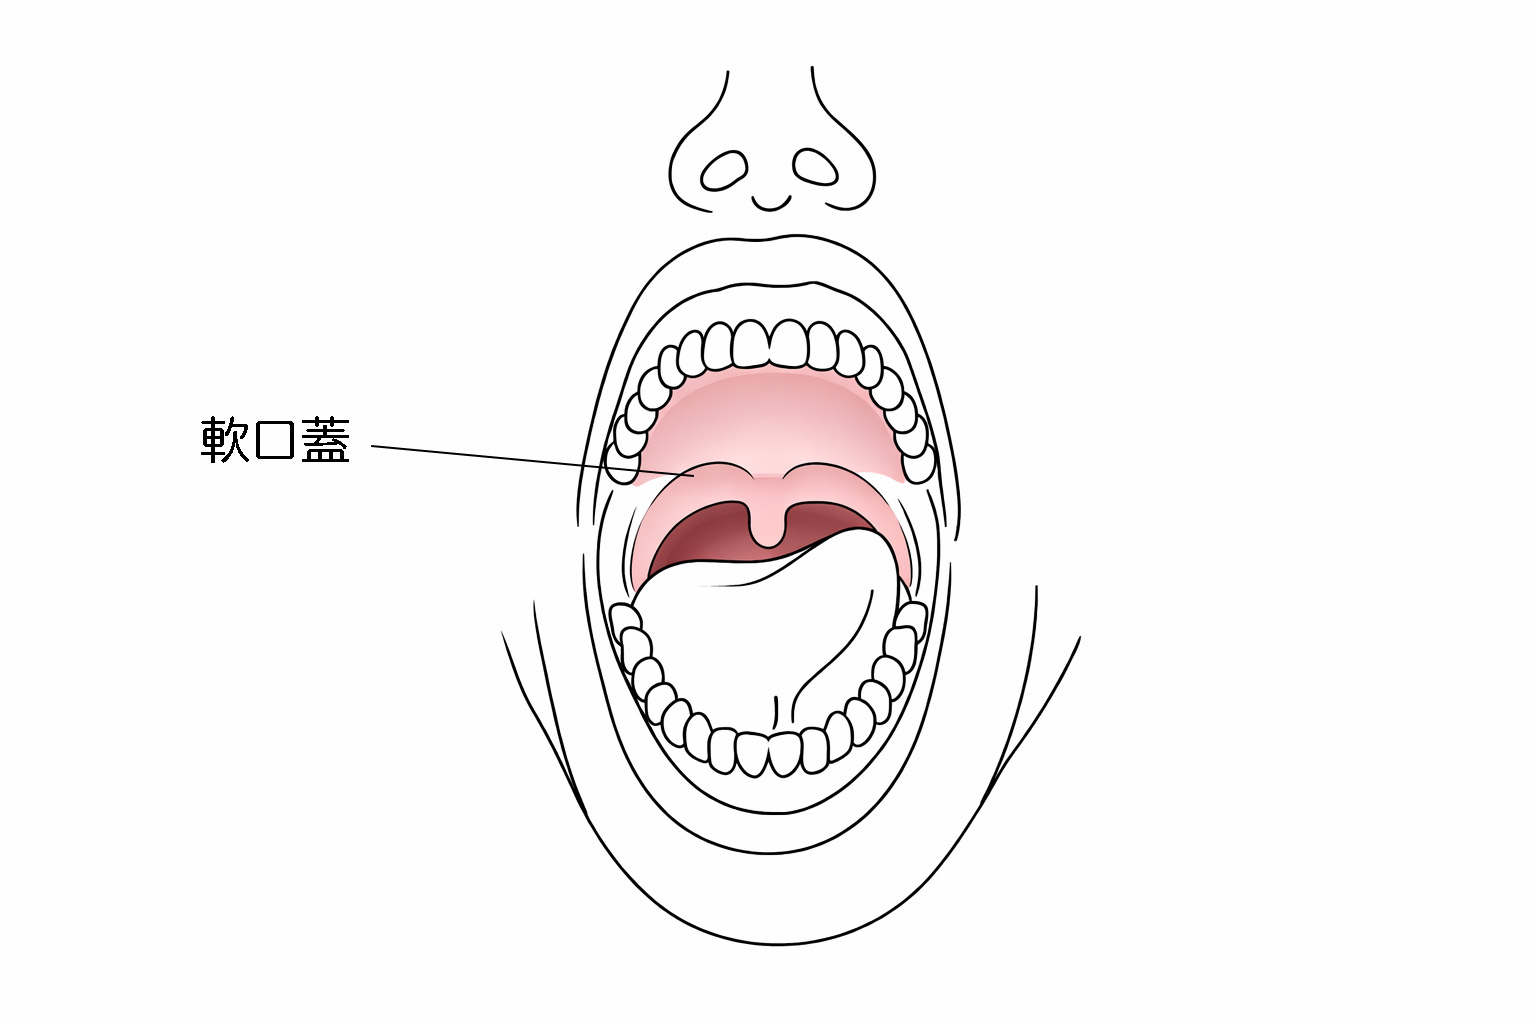

軟口蓋挙上装置とは

脳卒中などの後遺症で麻痺した口の奥の柔らかい部分(軟口蓋)を、押し上げる装置で、お口と鼻の間の空気漏れを抑えます。レジンと金属のバネでできており、上のあごに装着します。

麻痺などで動かなくなった軟口蓋を押し上げ、鼻への空気漏れを抑えます。

鼻で息をする時には、喉の奥と鼻は空気が通る状態になっていますが、発音を行ったり、食べ物を飲み込んだりするときは、鼻に逆流しないように、鼻と喉の奥をふさぐ(鼻咽腔閉鎖といいます)必要があります。この機能を果たしているのが「軟口蓋」ですが、この組織の大きさが生まれつき足りなかったり、腫瘍の手術などで失った場合に、その足りない部分を補うことを目的とする装置です。